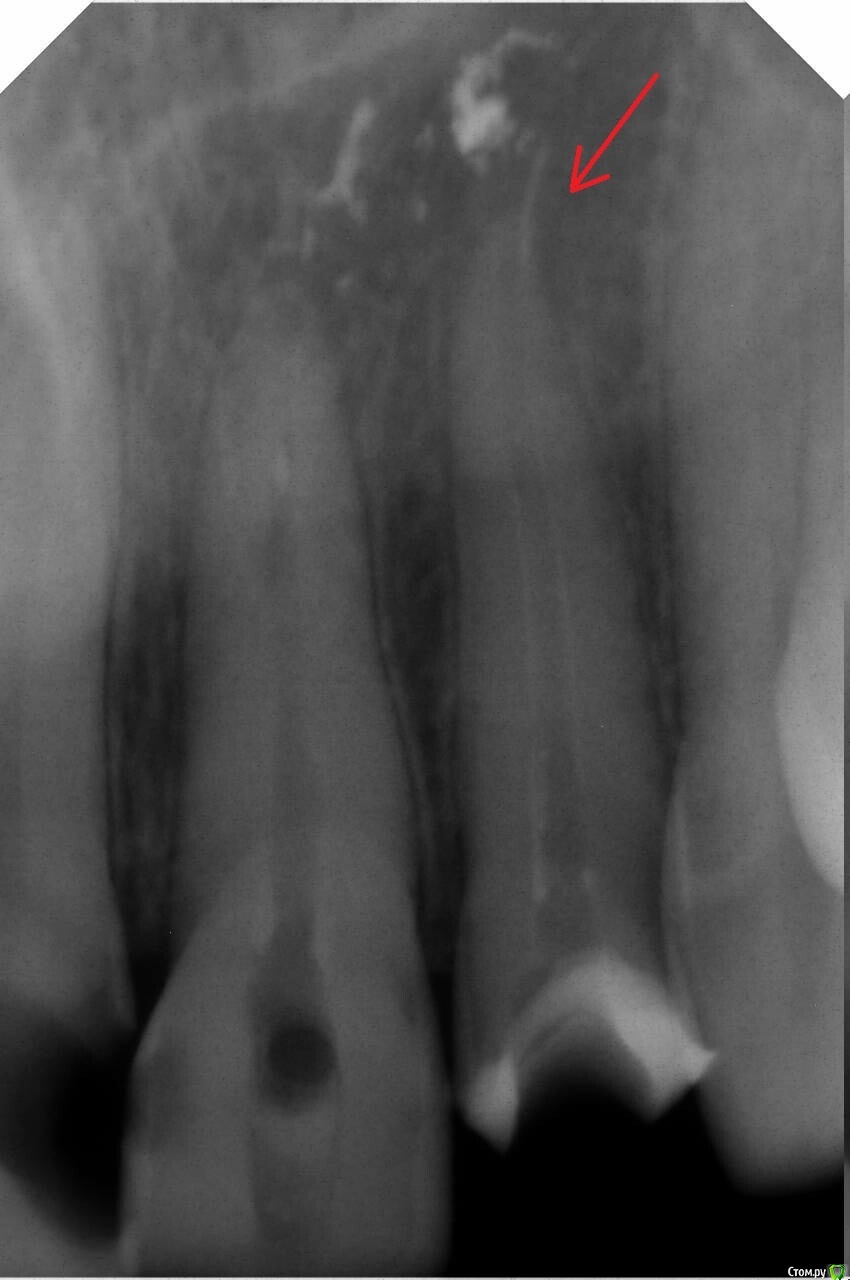

red_butler Опубликовано 27 октября, 2020 Поделиться Опубликовано 27 октября, 2020 Нужно сделать Кт, по этому снимку не понятно, где находится отломок, в зубе или уже нет Ссылка на комментарий

АнтонТЛТ Опубликовано 27 октября, 2020 Поделиться Опубликовано 27 октября, 2020 Будет безопаснее для зуба достать хирургически. По этому снимку обломок за изгибом канала, т.е. не в прямой видимости. Терапевтически если пытаться достать, то скорее всего зуб может сильно пострадать, т.к. придется сильно расширять канал чтобы увидеть обломок. Нужно сделать КТ, действительно обломок может полностью находиться за пределами зуба. Достать нужно, т.к. этот фрагмент через какое-то время может начать окисляться. 1 Ссылка на комментарий

Zlata-doctor Опубликовано 28 октября, 2020 Поделиться Опубликовано 28 октября, 2020 Какая резекция? Где здесь показания? Резекция верхушки корня делается при наличии очага воспаления. Где он здесь? Я бы предложила следующее.1. Точно установить, что есть отломок ( на снимке обычно металлические предметы визуализируются более контрастно, есть вероятность, что это след от пломбировочного материала), если есть, то определить локализацию ( сделать КТ).2. Провести качественную пломбировку корневого канала. Ортоградно ( через канал) пытаться извлечь отломок не надо-потеряете зуб.3. Определить необходимость извлечения отломка, если он есть. Я бы сделала контрольный снимок через полгода, год и тогда определила бы необходимость хирургического извлечения ( разрез на десне, аккуратный доступ к отломку, удаление его, швы-трогать корень не надо). 2 Ссылка на комментарий